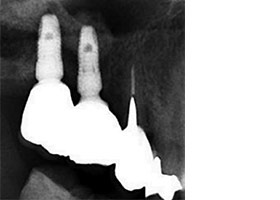

X光片顯示骨頭成功增高